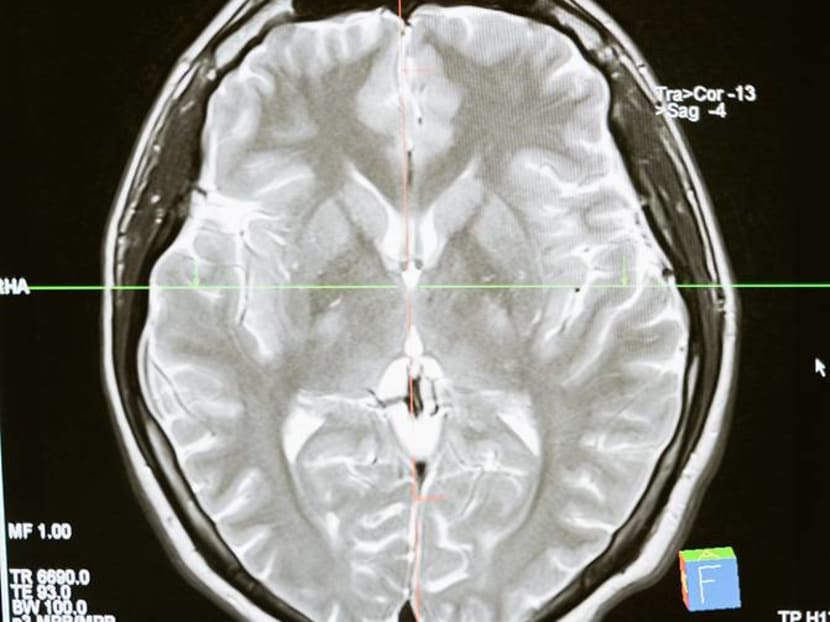

FILE PHOTO: A picture of a brain scan. (Photo: Pexels/Mart Production)

In a large study published in the journal Nature on Mar 7, a team of researchers in the UK investigated brain changes in people ages 51 to 81 who had experienced COVID-19.

The team found marked differences in grey matter - or the neurons that process information in the brain - between those who had been infected with COVID-19 and those who had not.

Specifically, the thickness of the grey matter tissue in brain regions known as the frontal and temporal lobes was reduced in the COVID-19 group, differing from the typical patterns seen in the people who hadn’t had a COVID-19 infection.

In the general population, it is normal to see some change in grey matter volume or thickness over time as people age. But the changes were more extensive than normal in those who had been infected with COVID-19.

Interestingly, when the researchers separated the individuals who had severe enough illness to require hospitalisation, the results were the same as for those who had experienced milder COVID-19.

That is, people who had been infected with COVID-19 showed a loss of brain volume even when the disease was not severe enough to require hospitalization.

Finally, researchers also investigated changes in performance on cognitive tasks and found that those who had contracted COVID-19 were slower in processing information than those who had not.

This processing ability was correlated with volume in a region of the brain known as the cerebellum, indicating a link between brain tissue volume and cognitive performance in those with COVID-19.